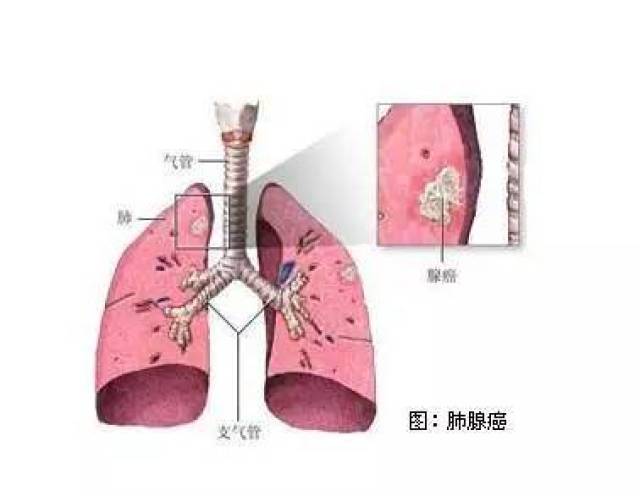

- 肺癌,为啥是"癌"

- 非细胞肺癌复发 图片合集

- 肺癌咳出肿瘤组织图片图片